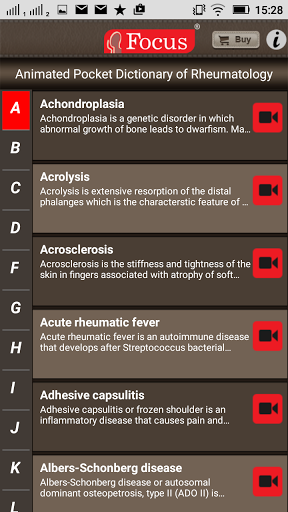

The FOCUS Animated Pocket Dictionary of RHEUMATOLOGY is the first ever animated dictionary in the subject. A valuable reference for physicians and students alike, it covers 100 rheumatology related terms and definitions. All the definitions have been graphically described with the help of 3D animations and are accompanied by text definitions.

The Focus Animated Pocket Dictionaries are the world’s first ever animated dictionaries that provide definitions of medical terms with the aid of realistic and narrated 3D animations, complimented with text definitions. Terms arranged alphabetically making definitions easy to search. These unique visual dictionaries are excellent reference sources for health professionals, students and health consumers. The videos play independent of the internet once downloaded.